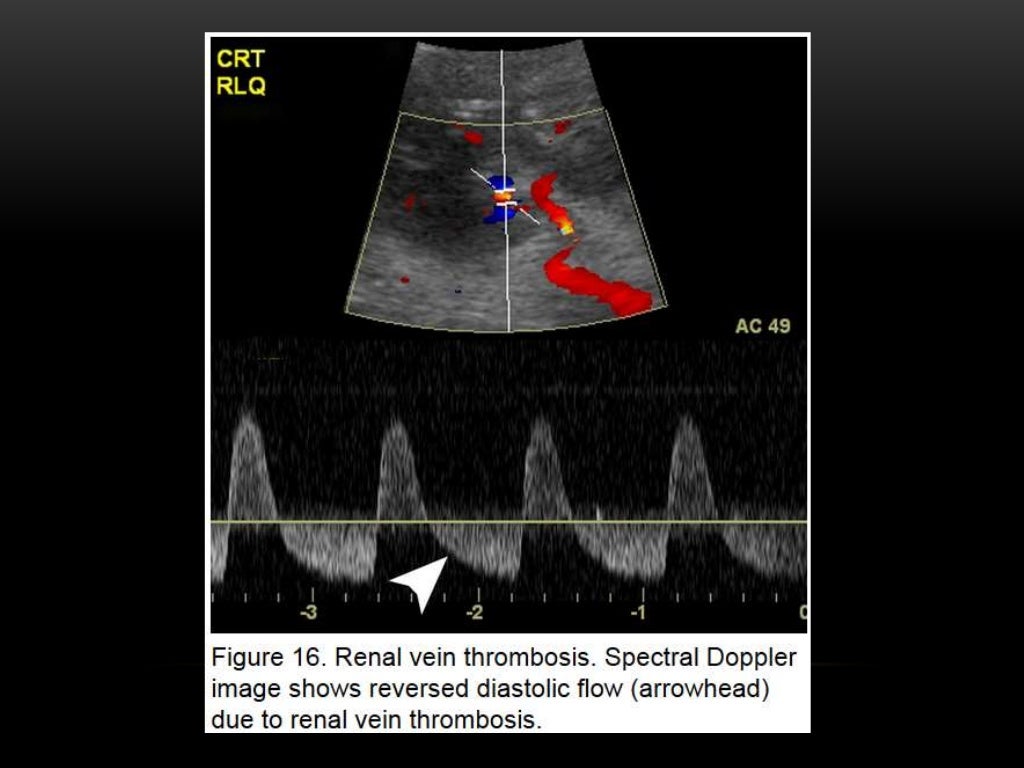

WebLa ecografía Doppler es una prueba no invasiva que calcula el flujo de la sangre en los vasos sanguíneos haciendo rebotar ondas sonoras de alta frecuencia. WebSi te van a realizar una ecografía-doppler estas son las cuestiones que debes tener en cuenta: Duración : la ecografía-doppler dura unos 15 minutos. Ingreso : se suele realizar. WebDE LA ARTERIA RENAL MEDIANTE DOPPLER La estenosis de la arteria renal mediante la técnica Doppler se detecta de dos formas: 1) por la alteración de la forma de onda en.